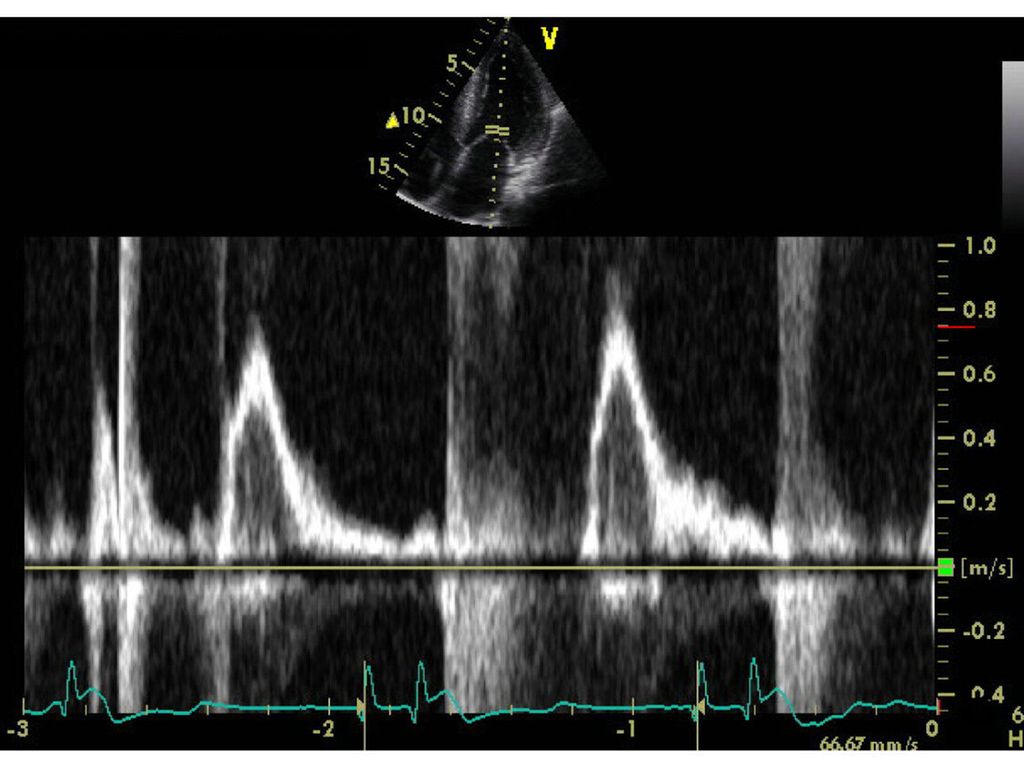

Fokus rechtes Herz 2021

Fokus rechtes Herz 2020